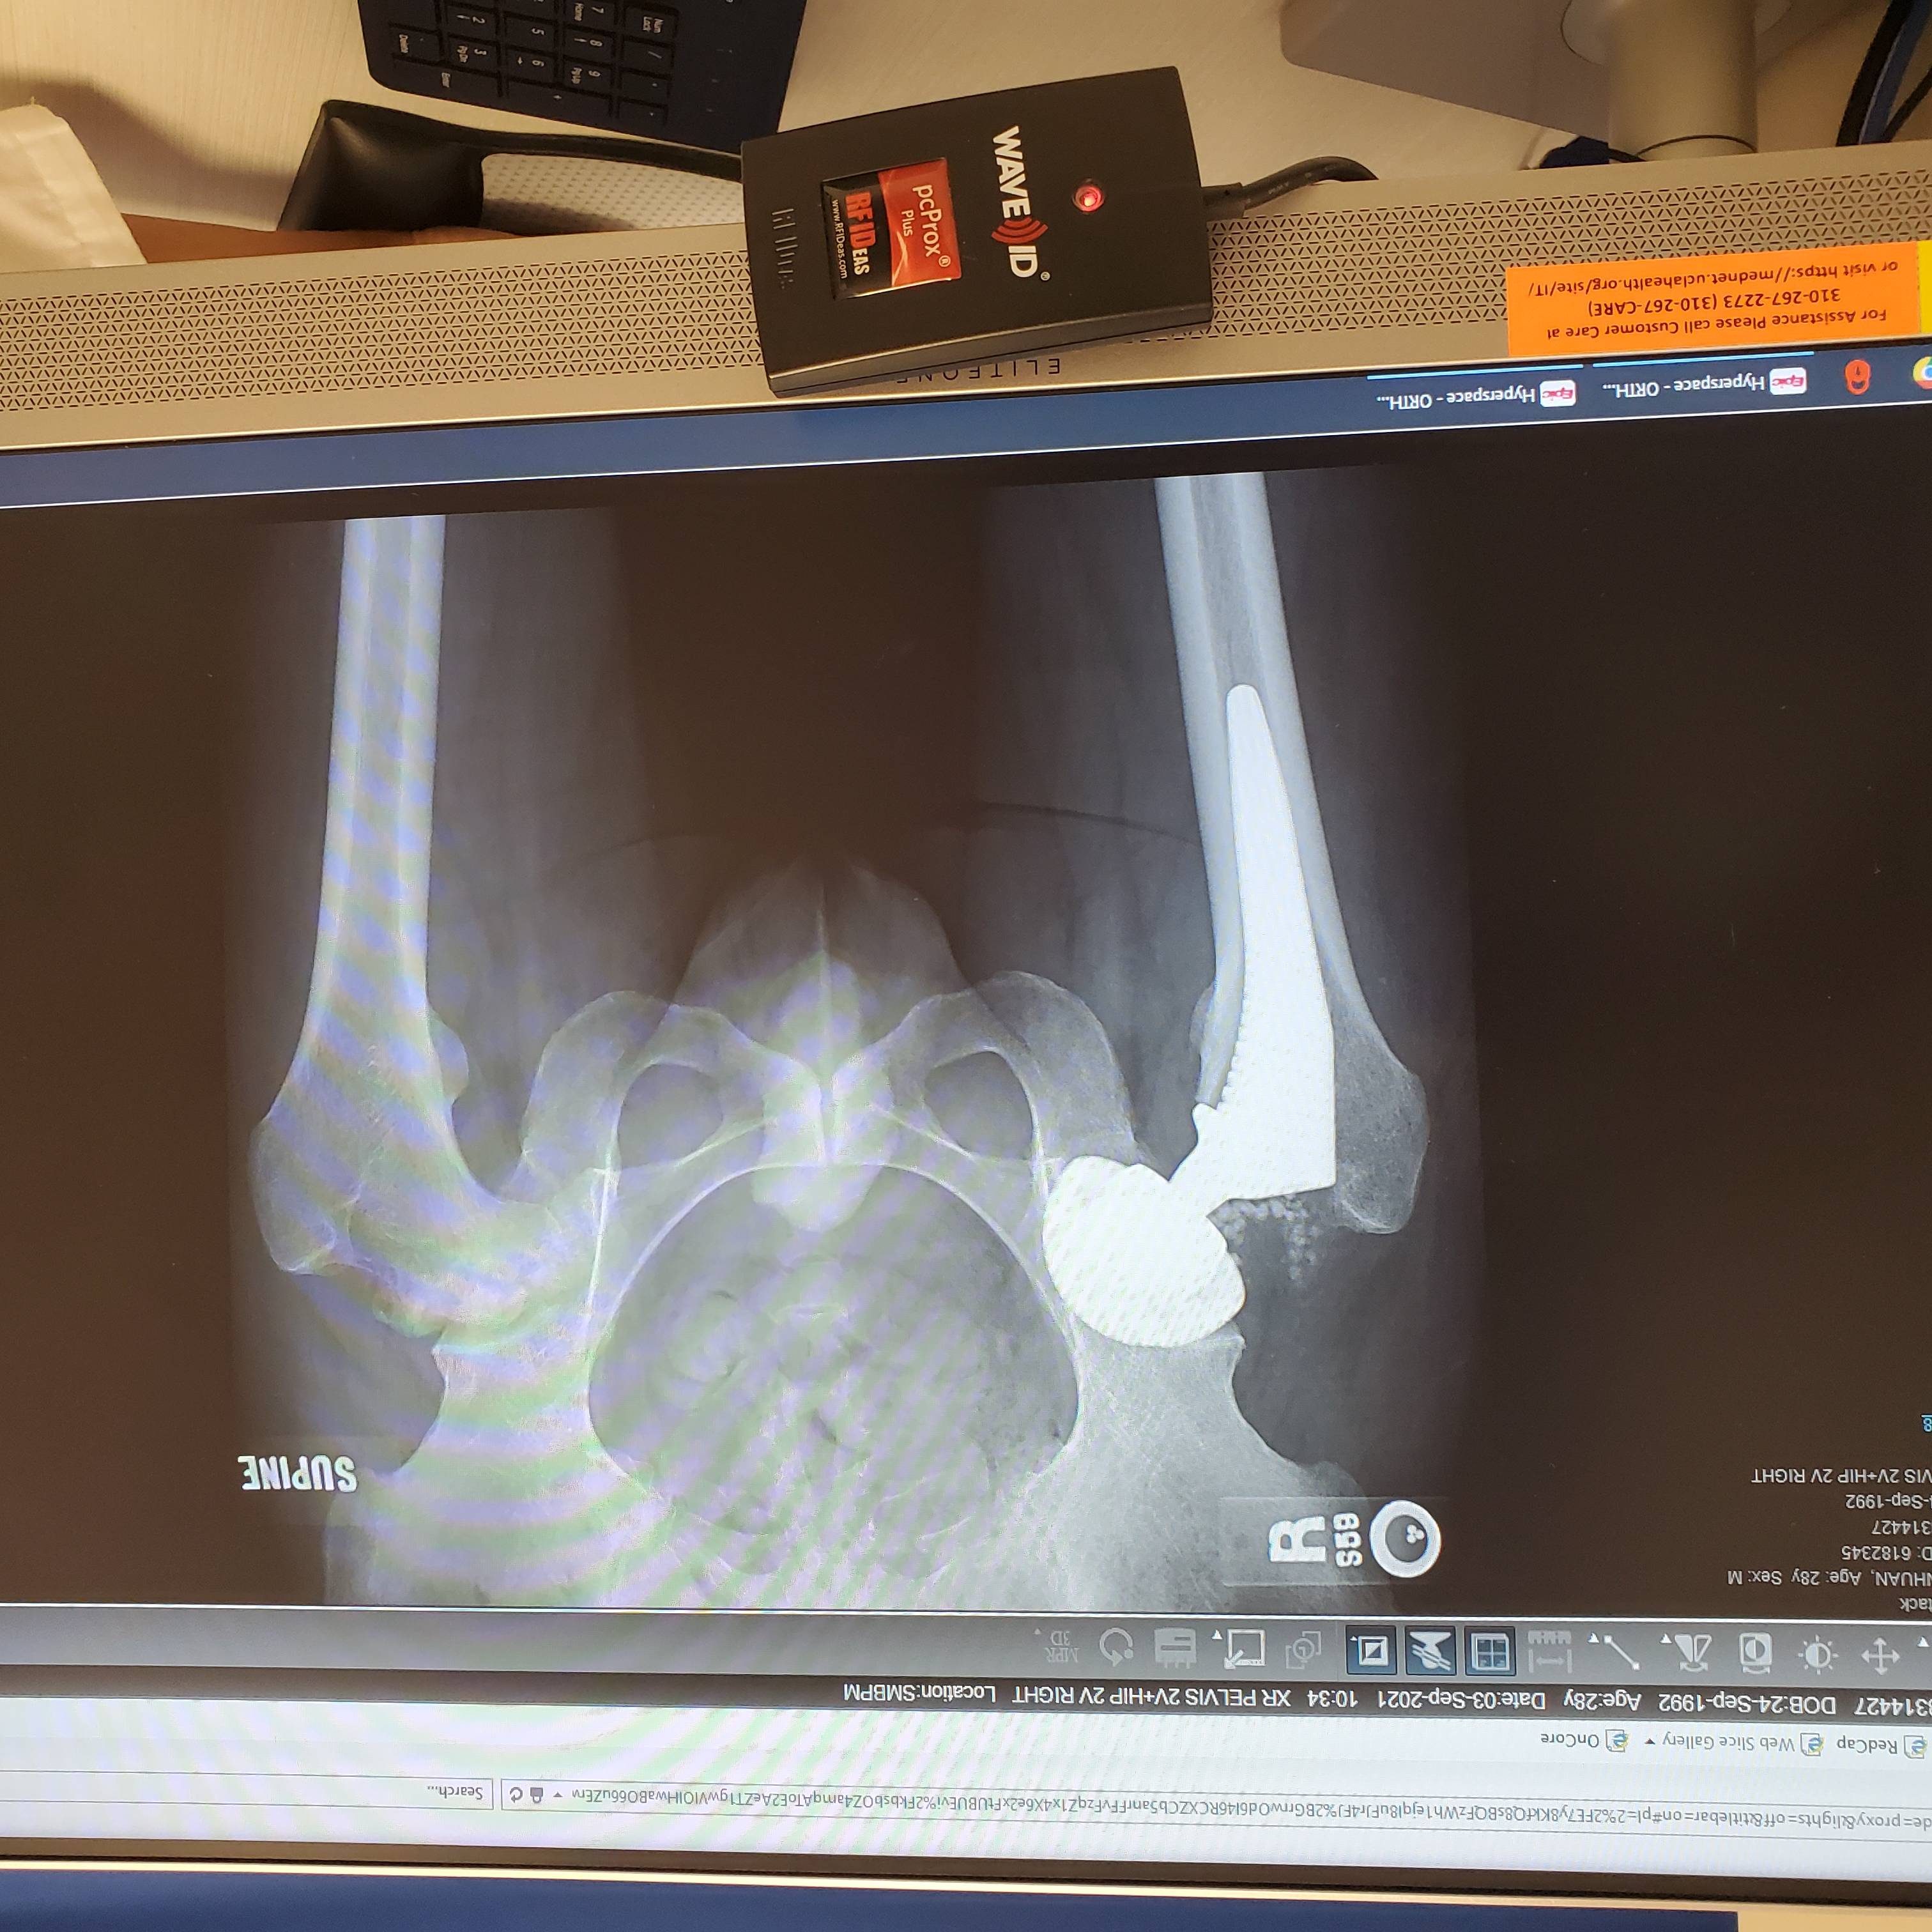

右侧置换一个月

右侧置换一个月,正常走路没任何问题,刀口附近感觉有点麻痹。

左侧严重恶化,站立久了会疼痛。

置换以后感觉穿袜子有点困难,不知道做过置换的你们是怎么样的? 多久可以下蹲?